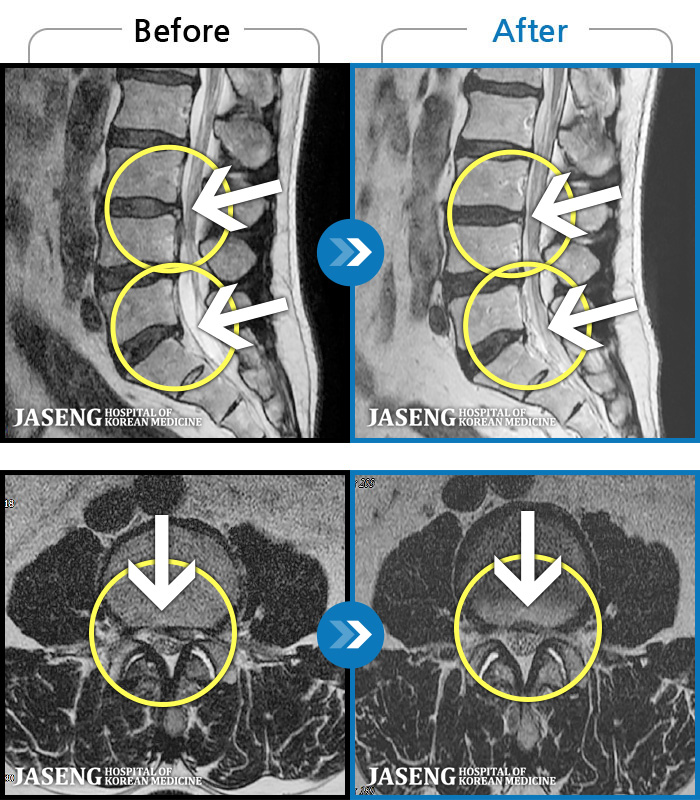

MRI ġ

1,245 MRI ũ ʸ Ȯϼ.